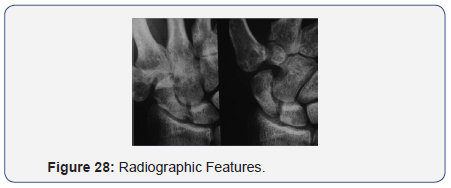

- Maintenance of joint space despite subluxation of the 1st MC on the Scaphoid on radial deviation of the wrist.

- Stress views of the wrist:

- No changes = 9 wrists

- Widening of the Sc-Trap.Jt =12 wrists

- Widening of the Sc-Cap.Jt = 6 wrists

- Widening of gap between the bases of 1st & 2nd MC’s = 6 wrists (Figures 26-28).